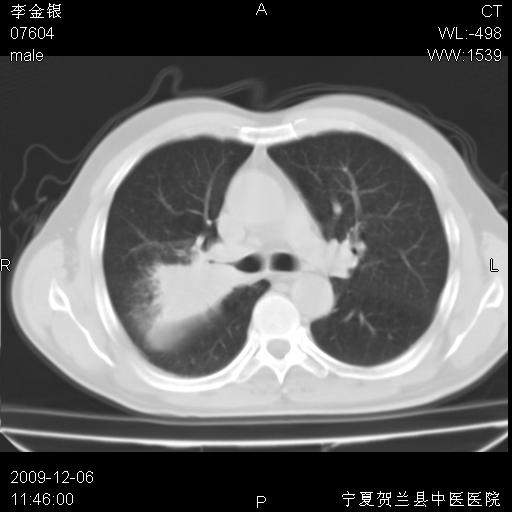

该病人 ,男,62岁,主因咳痰带血两天

考虑右肺中央型占位性病变并阻塞性肺炎.(右肺上叶支气管变窄),建议支纤镜检查.

考虑右肺中心型肺癌伴阻塞性肺炎及右肺门淋巴结转移,建议纤维支气管镜进一步检查。

支气管壁明显增厚 管腔狭窄,腔静脉后多个淋巴肿大,结合年龄病史考虑右肺上叶中央型肺癌并阻塞性肺炎

右肺上叶后段支气管阻塞,右上肺门占位,相应肺段阻塞性肺炎,右肺门有淋巴结肿大。诊断右肺上叶中心型肺癌,阻塞性肺肺炎、右肺门淋巴结转移。

右上叶支气管狭窄,管壁增厚,远端斑片状软组织影,病灶邻近叶间裂,叶间裂无移位。

诊断右肺中央型肺癌。

那个片影应该大部分都是病灶,病灶沿肺段支气管分支生长,后段完全显示不清、闭塞。若为不张应该伴有叶裂的移位,若为炎症应有空气支气管征。

考虑右侧中央型肺癌伴右肺上叶后段阻塞性炎症、肺不张、右肺门和纵隔淋巴结肿大。

右肺上叶中心型肺癌,阻塞性肺炎、右肺门和纵隔淋巴结转移。